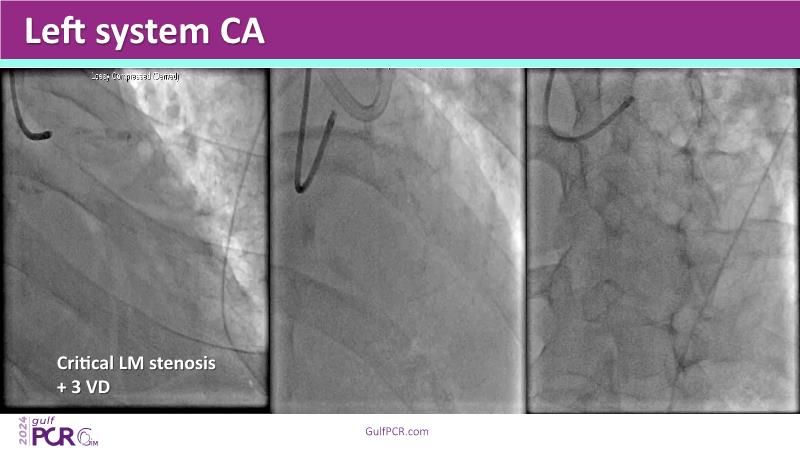

This session highlights the essential role of mechanical circulatory support (MCS) in managing high-risk PCI and AMI-related cardiogenic shock. Explore case-based discussions on device selection, hemodynamic impact, and evidence-based strategies to optimize outcomes in complex scenarios.